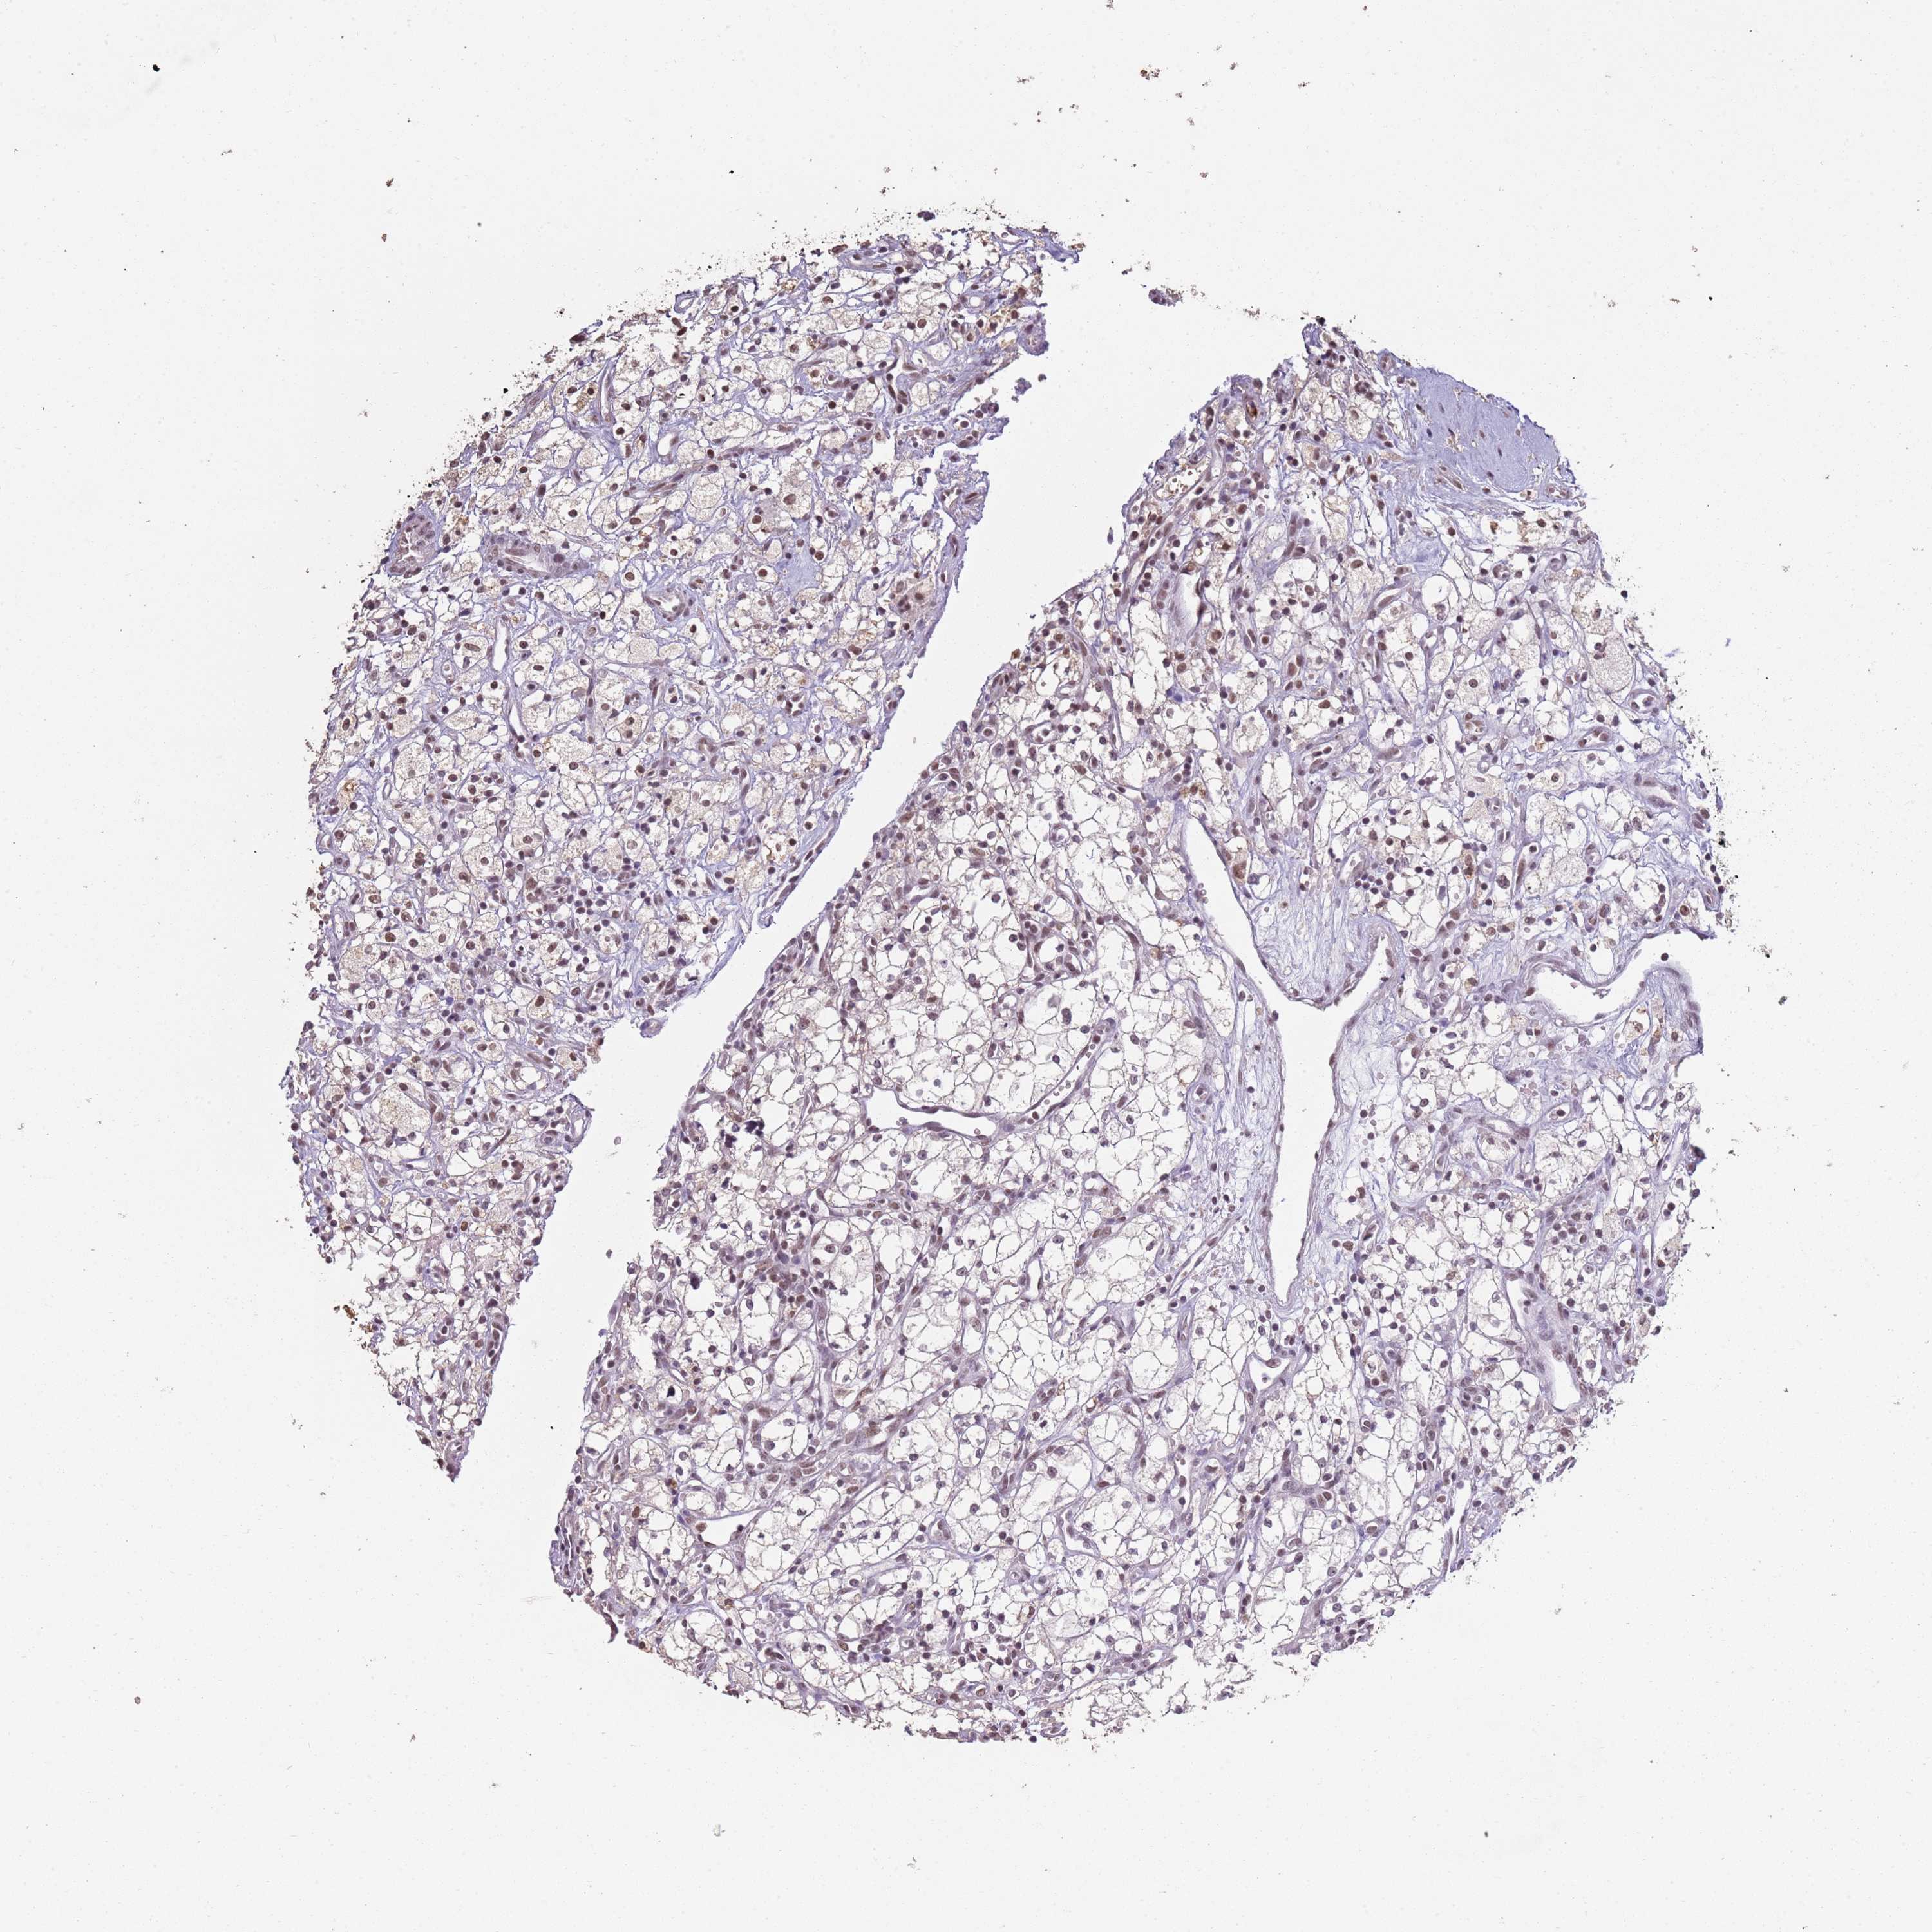

ARL14EP is validated prognostic, high expression is favorable in Kidney Renal Clear Cell Carcinoma (TCGA)

Best expression cut offi

When clicking on this number, the vertical dashed line indicating cut-off, the interactive survival plot, and the Kaplan-Meier curve will be adjusted to show results based on the best expression cut-off.

: 12

P scorei

N/A

5-year survival highi

5-year survival lowi

Average pTPM 15.2

Number of samples 521